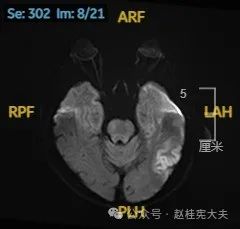

头颅磁共振平扫提示左侧颞枕叶亚急性期脑梗死可能。头颈部CTA示左侧椎动脉颅内段发育不良。头颅磁共振增强+波谱分析提示左侧颞枕叶病灶,考虑脑炎可能大。

患者3个半月前的颅脑磁共振片子见下方视频号:患者此次发病在当地医院做的磁共振片子下方视频号:

以上为患者发病后3次的颅脑磁共振片子,临床诊断基本上可以确认了,希望患者逐渐恢复!